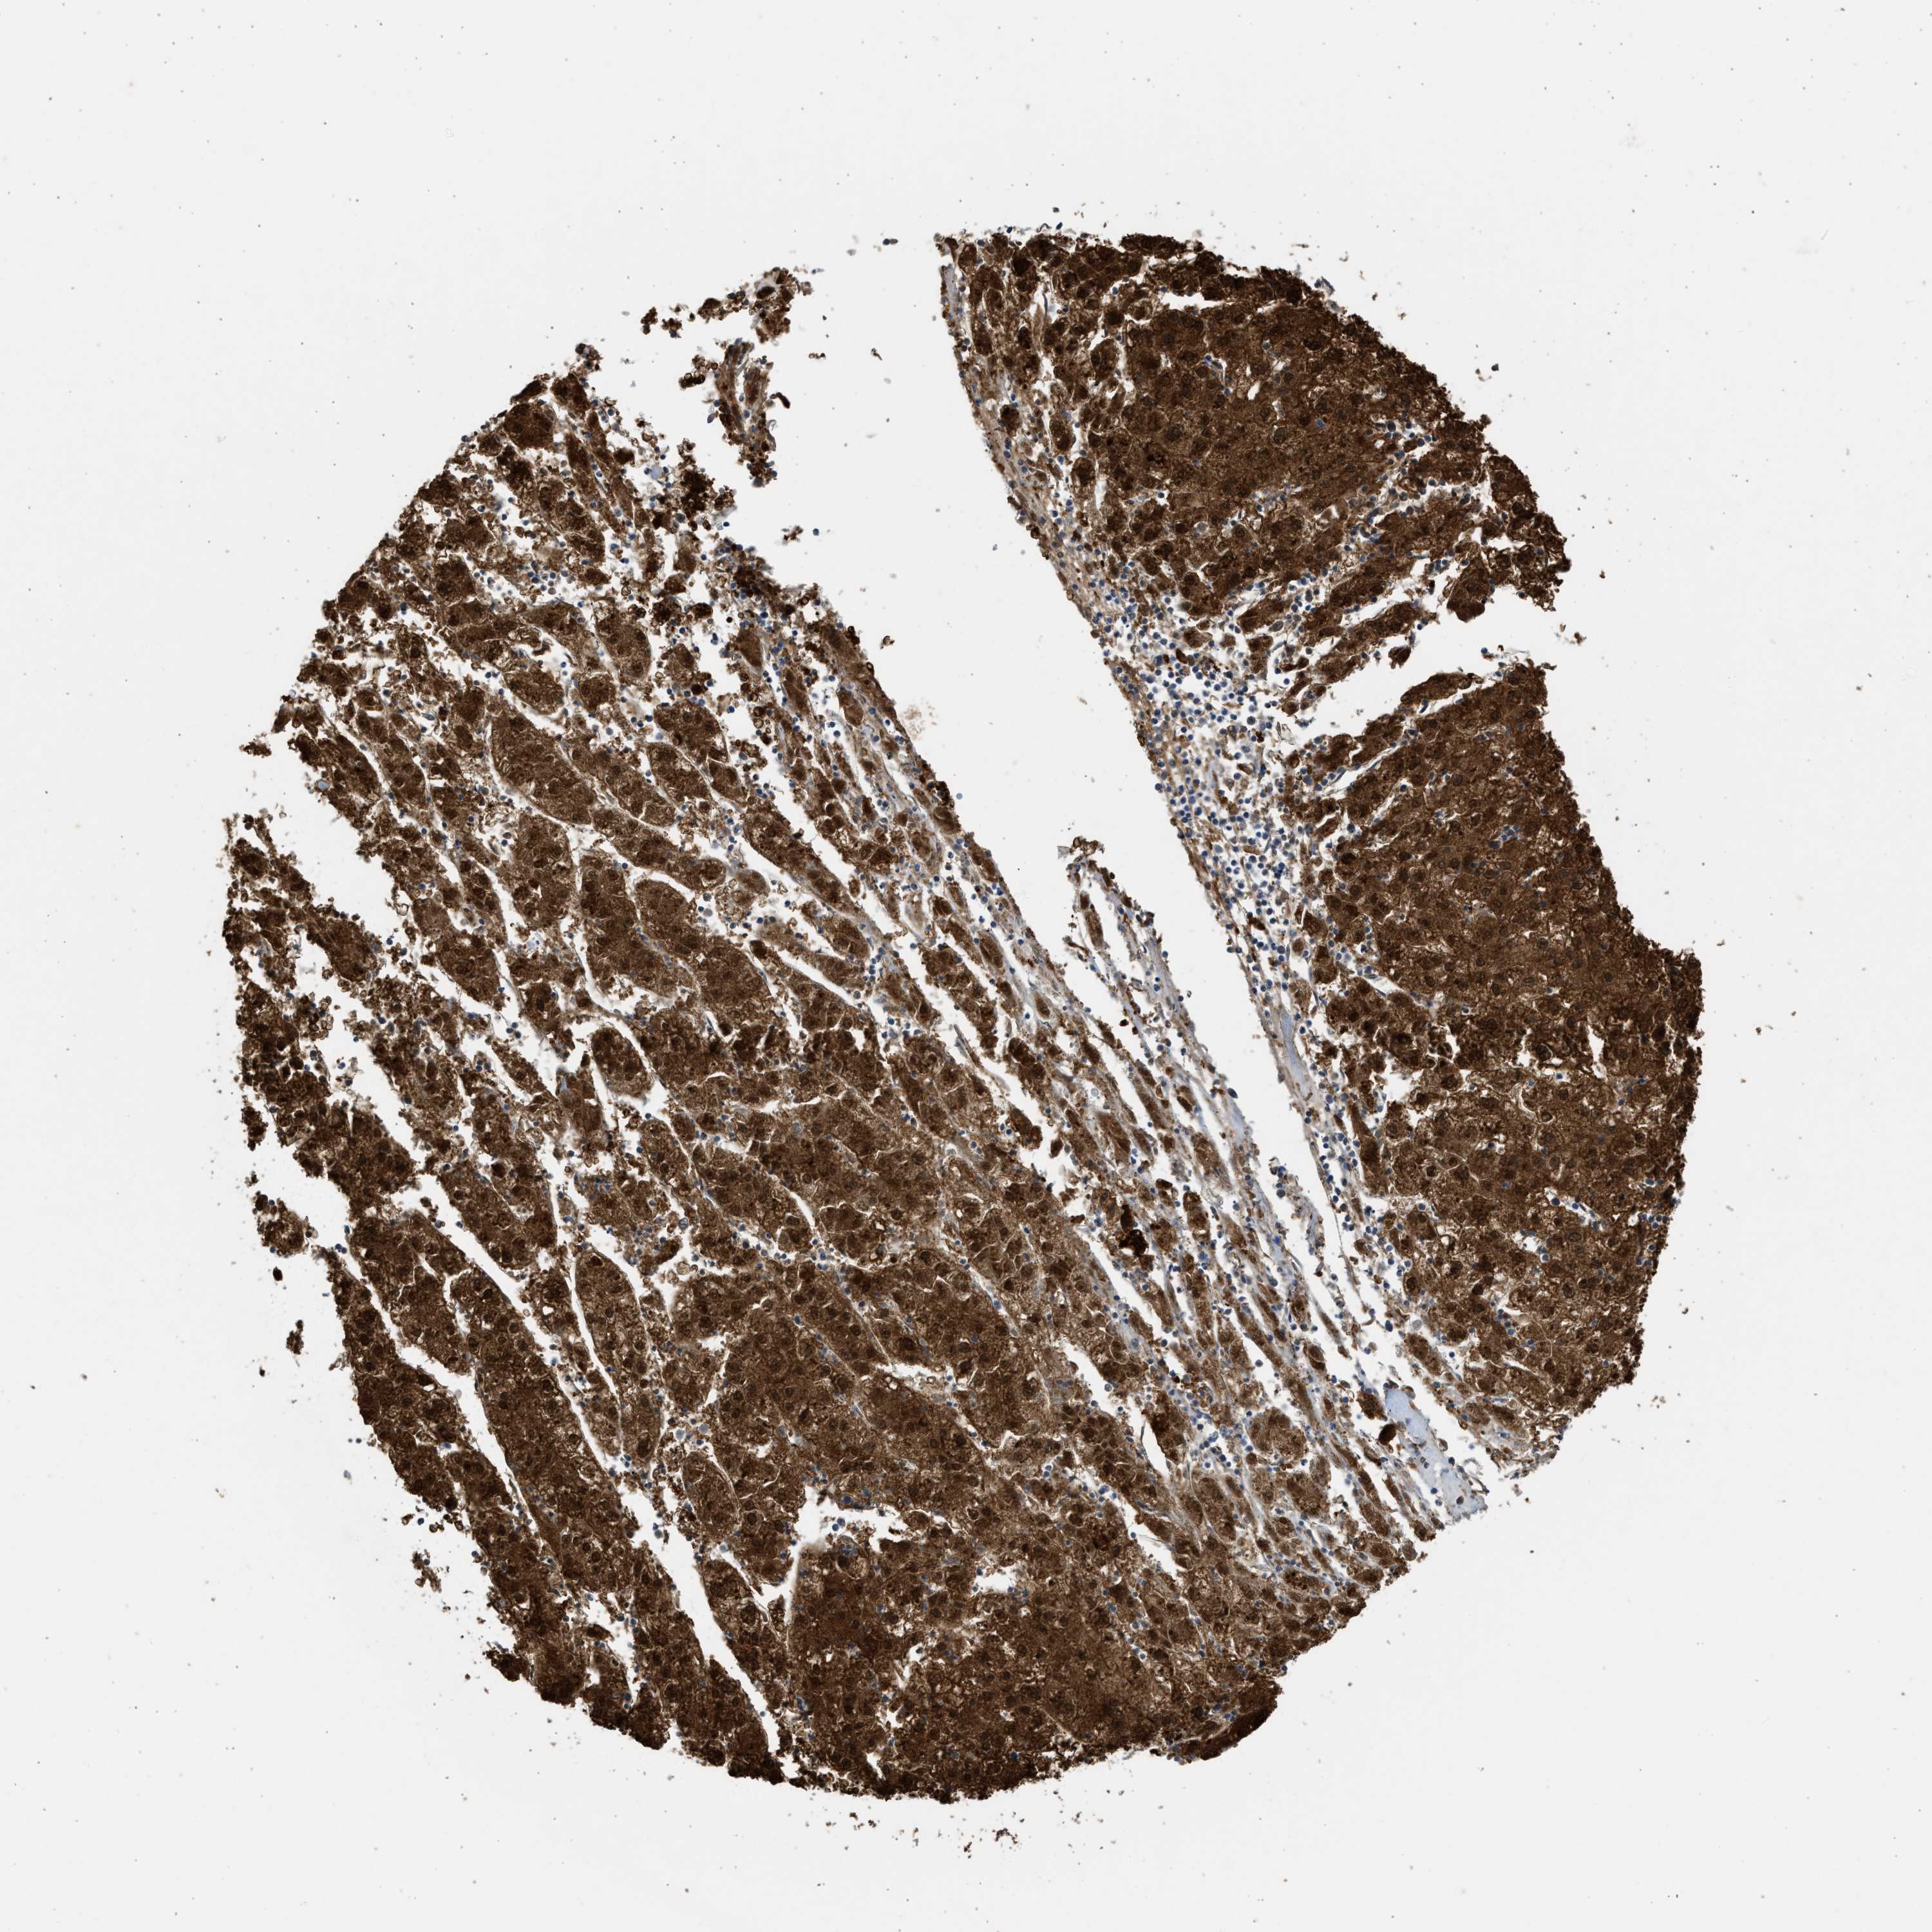

LIVER CANCER - Protein expressioni

A mouse-over function shows sample information and annotation data. Click on an image to view it in a full screen mode. Samples can be filtered based on level of antibody staining by selecting one or several of the following categories: high, medium, low and not detected. The assay and annotation is described here.

Note that samples used for immunohistochemistry by the Human Protein Atlas do not correspond to samples in the TCGA dataset.

Antibody stainingi

Antibody staining in the annotated cell types in the current human tissue is reported as not detected, low, medium, or high, based on conventional immunohistochemistry profiling in selected tissues. This score is based on the combination of the staining intensity and fraction of stained cells.

Each image is clickable and will lead to virtual microscopy that enables deeper exploration of all samples and also displays staining intensity scores, fraction scores and subcellular localization as well as patient and tissue information for each sample.

Antibody HPA041487

Antibody HPA063633

Antibody CAB018755

Staining

High

Medium

Low

Not detected

Intensity

Strong

Moderate

Weak

Negative

Quantity

>75%

75%-25%

<25%

None

Location

Nuclear

Cytoplasmic/membranous

Cytoplasmic/membranous,nuclear

Cholangiocarcinoma

Carcinoma, Hepatocellular, NOS